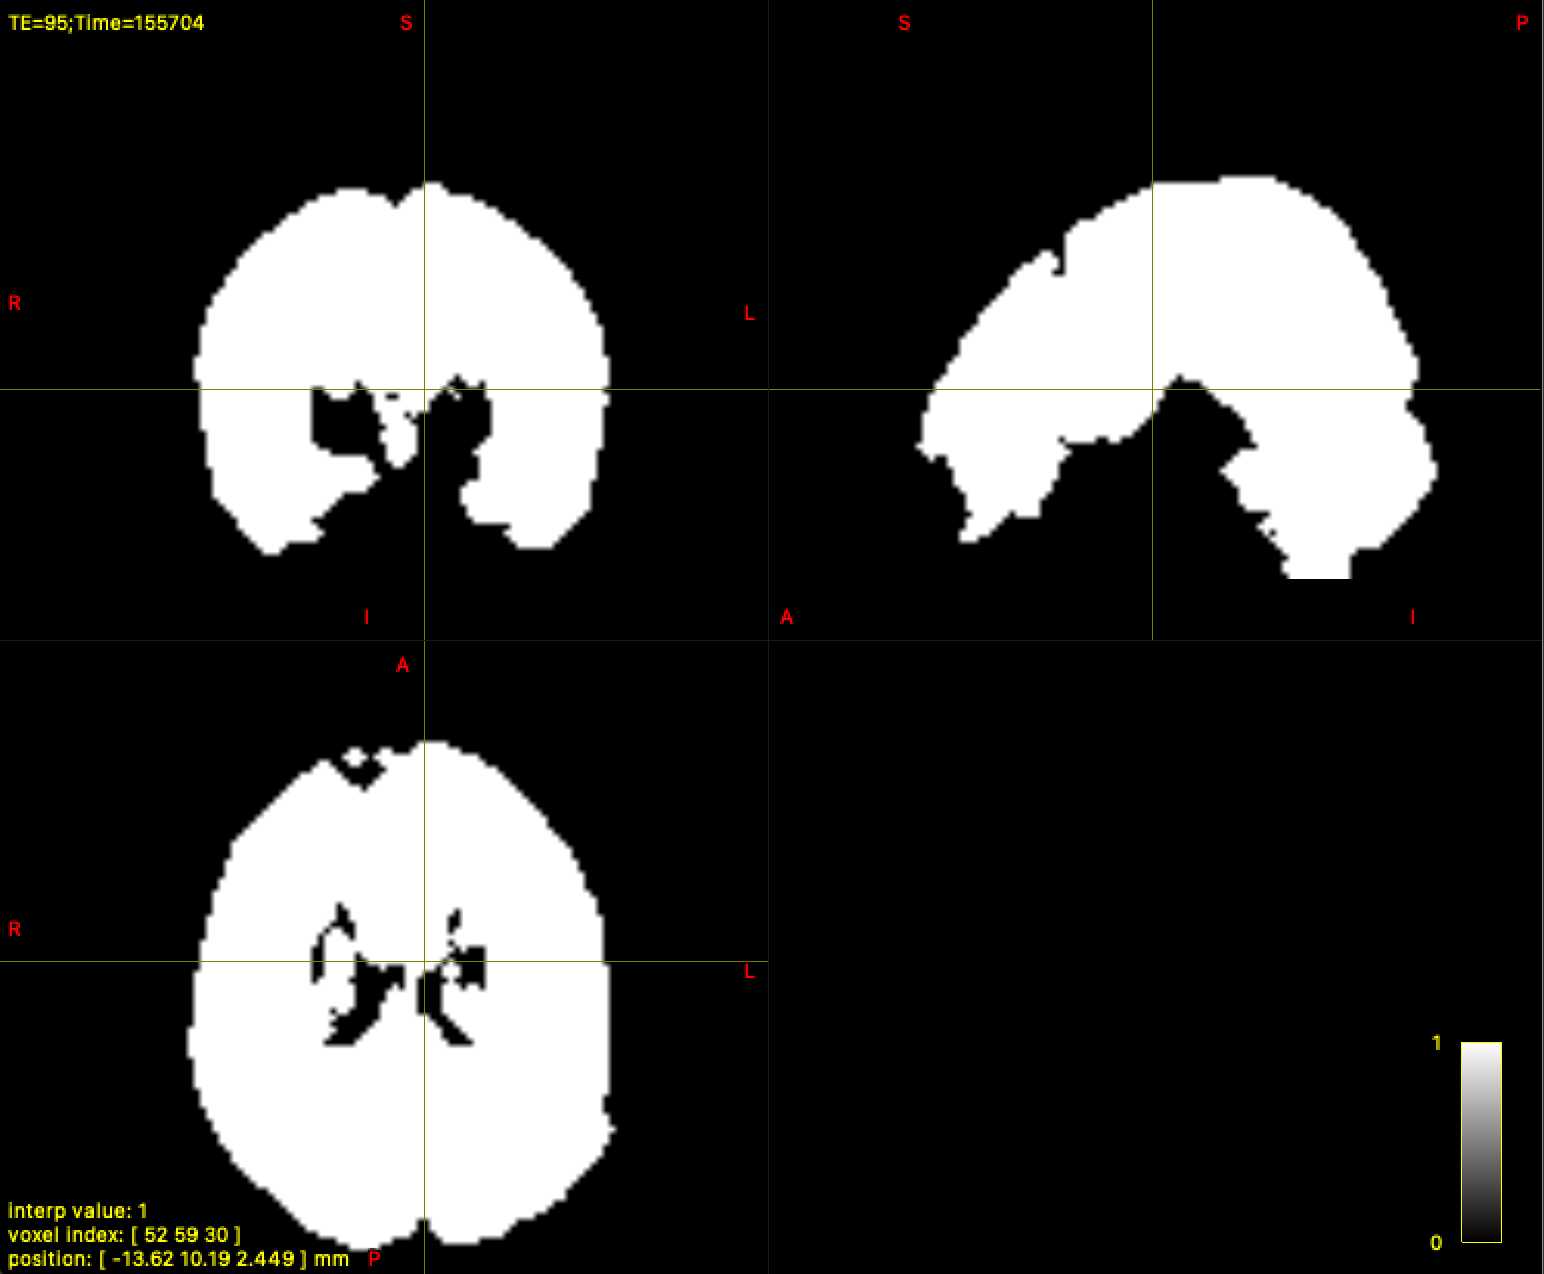

For most subjects, the dwi_mask_unbiased.mif was correctly generated. However, in 9 subjects, dwi2mask produces a completely white mask (i.e., the entire field of view is white instead of a brain-shaped mask).

p.s. The following image is the dwi_denoised_unringed_preproc_unbiased.mif of the above masks: